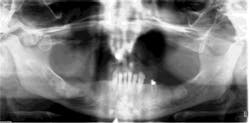

Medical diagnosis: Multiple myeloma

Drug therapy: Aredia 16 months; Zometa 14 doses

Dental treatment: Two months chlorhexidine gluconate and clindamycin. Root canal tooth #20 to avoid extraction. Patient was asked to avoid mandibular partial denture. Three-month hygiene recare with fluoride trays.

Photo courtesy of Drs. Robert E. Marx and Richard A. Kraut